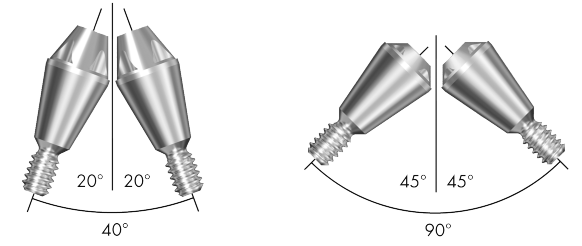

Conical Seal Design – a strong and stable fit

A conical connection that seals off the interior of the implant

from surrounding tissues, minimizing micromovements and microleakage.